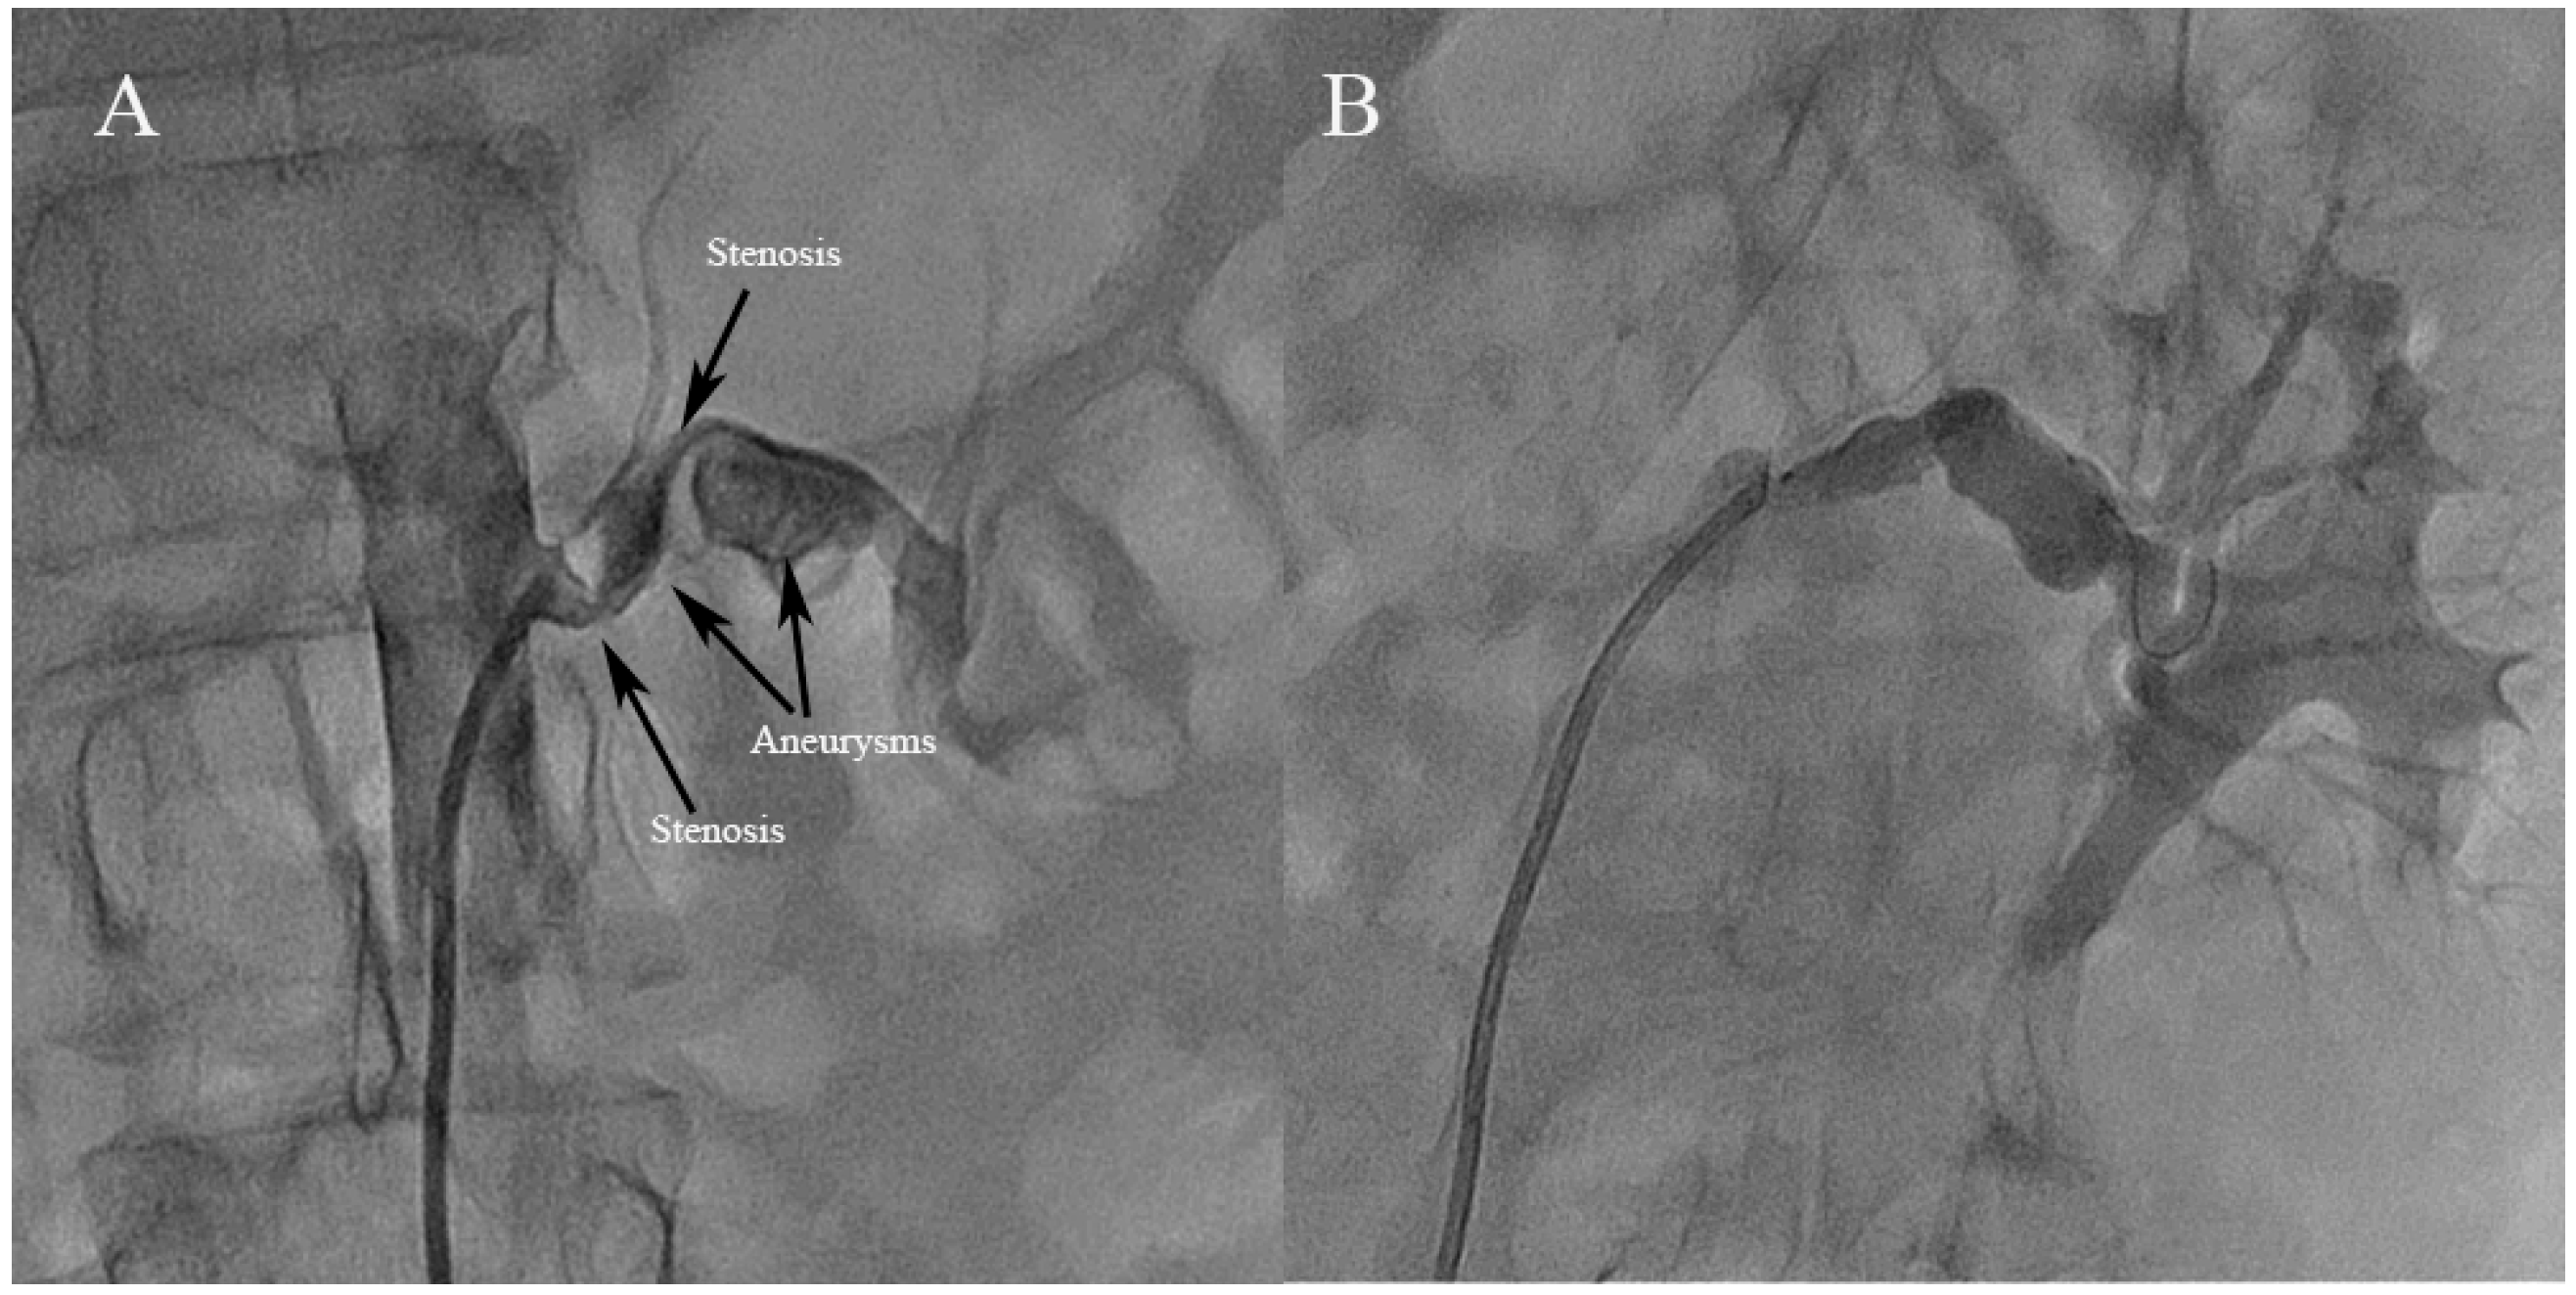

3.2. Angiographic Findings and Treatment